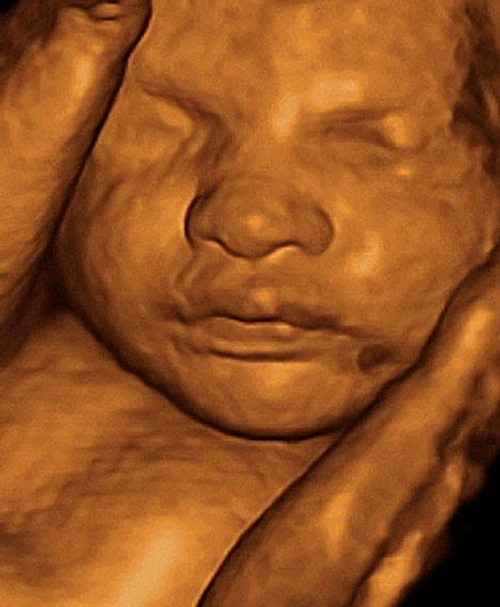

Ecografiile 3D şi 4D îţi arată cu cine o să semene bebeluşul

Indiferent de aparat,cele mai multe ecografiise fac 2D. Adică prin ecografia 3D,se vizualizează,se analizează şi se strâng laolaltă date obţinute tot dintr-o imagine 2D. 4D înseamnă că se obţin imagini 3D,dar în timp real. Timpul este astfel cea de-a 4-a dimensiune. Ecografele 3D şi 4D sunt mai bune decât 2D doar în anumite anomalii sau pentru analizarea anumitor organe. De exemplu,ce fac ecografele 3D şi 4D spre deosebire de 2D – reconstrucţie facială.